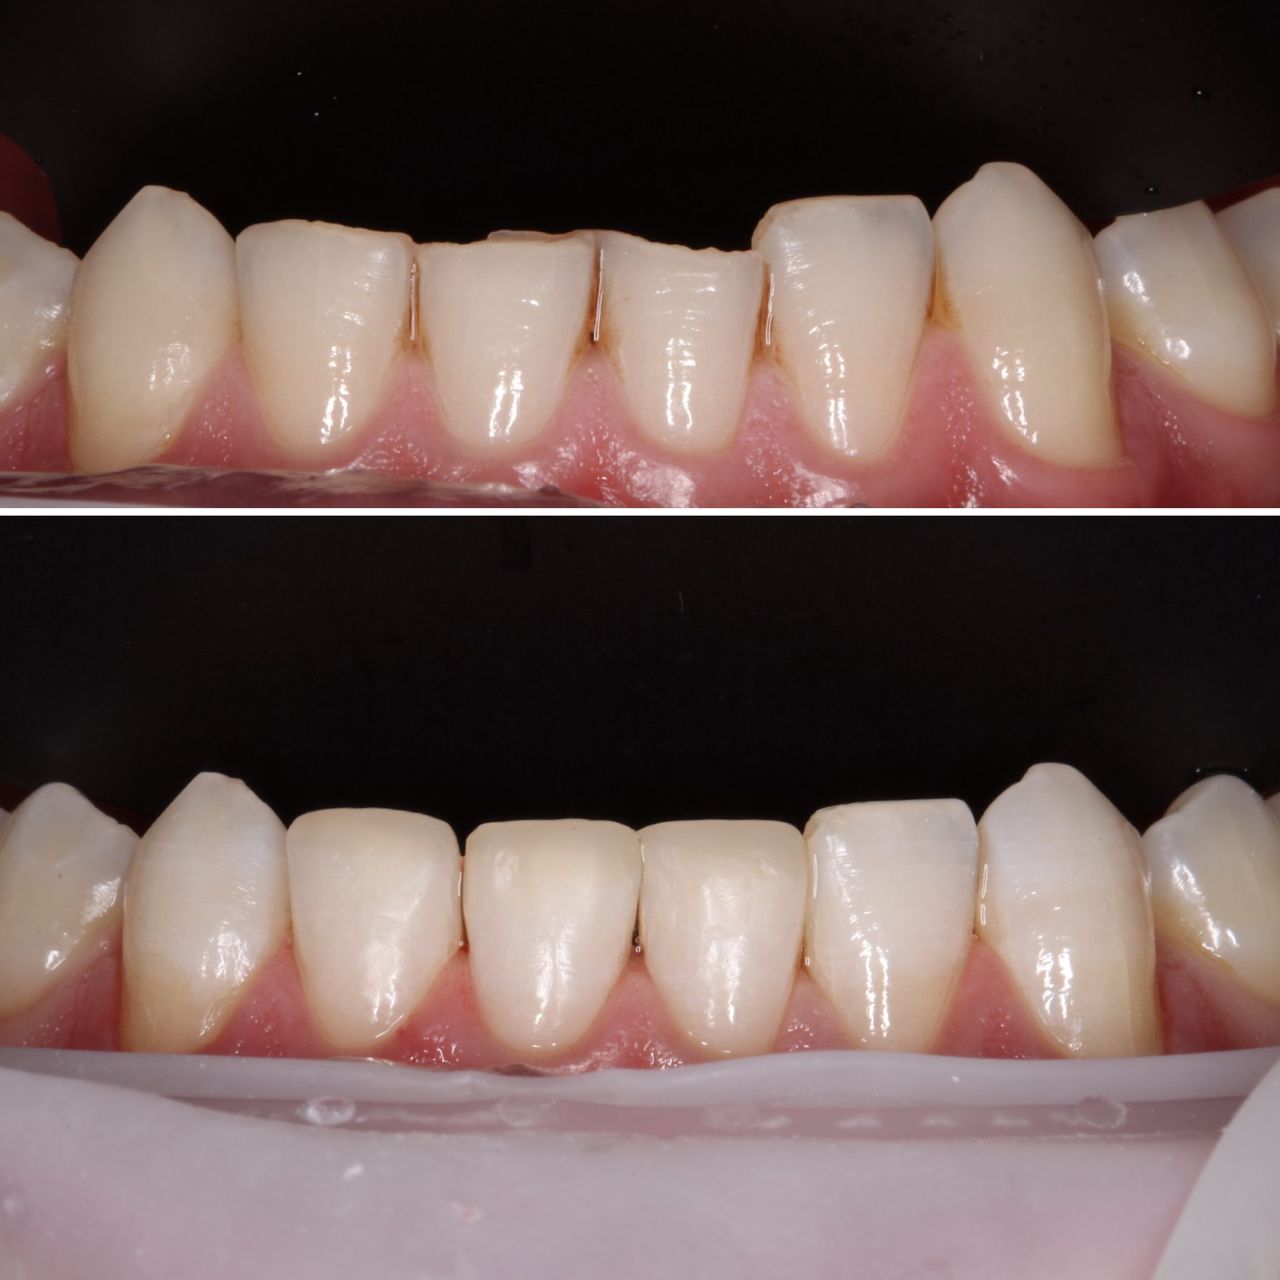

Jej pasją jest leczenie zachowawcze, wypełnienia z jej ręki są małymi dziełami sztuki, idealnie i anatomicznie wykończonymi. Precyzja i cierpliwość w sposobie pracy w połączeniu z wysokim poczuciem estetyki umożliwiły tej naturalny rozwój w kierunku stomatologii estetycznej. Dr Valeriia wykonuje precyzyjne kompozytowe odbudowy zębów przednich, bondingi oraz prace „z ręki”.

Doktor uważa, że obraz mówi więcej niż słowa, zapraszamy do zapoznania się z galerią jej prac.